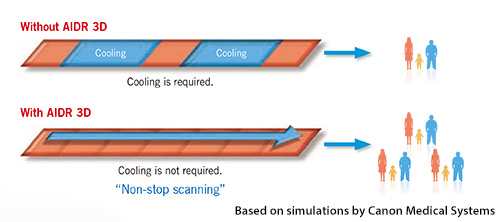

Технология AIDR 3D обеспечивает низкую дозу, превосходное качество изображения и отличную производительность. Благодаря этому время охлаждения прибора сокращается, поэтому можно проводить больше исследований в течение рабочего дня.